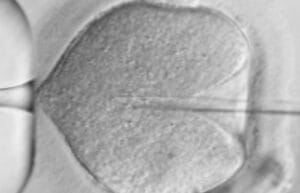

Intracytoplasmic Sperm Injection (ICSI) is a specialised IVF procedure where a single healthy sperm is carefully injected into an egg to achieve facilitate fertilisation.

At Sincere Healthcare Group, ICSI is routinely performed in most IVF cycles by our experienced embryology team within a tightly regulated laboratory environment. Our IVF lab operates with 24/7 temperature and air quality monitoring, supported by advanced incubators and equipment designed to maintain stable conditions for fertilisation and embryo development.

Time-lapse monitoring – Our embryology team monitors fertilisation, tracks embryo development daily, and refreshes the culture environment as needed—ensuring stable temperature, humidity, and gas levels at all times. They can observe exactly when cells divide and how each embryo develops. Embryos are assessed based on:

• Morphology – cell size, symmetry, and appearance

• Developmental timing – how quickly and evenly the cells divide

These objective markers help determine which embryos may be suitable for transfer or freezing, supporting decision-making throughout the IVF process.